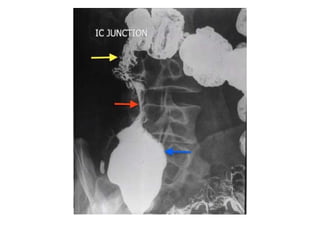

• 32.

OTHER SIGNS- • Conicalcaecum- shrunken in size and pulled out of the iliac fossa due to contraction and fibrosis of the mesocolon. The hepatic flexure may also be pulled down. • Early involvement of the ileocaecal region manifesting as spasm and oedema of the ileocaecal valve. Thickening of the lips of the ileocaecal valve and/or wide gaping of the valve with narrowing of the terminal ileum (“Fleischner” or “inverted umbrella sign”) are characteristic.

• 33.

• “String sign”– persistant narrow stream of barium indicating stenosis. • Purse string stenosis– localized stenosis opposite the ileocaecal valve with a rounded off smooth caecum and a dilated terminal ileum.